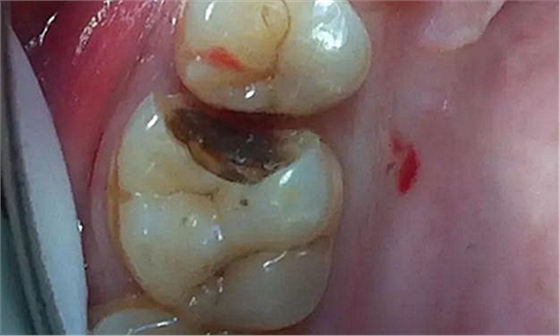

最后附幾例一次性根管治療+冠延長手術(shù)+高嵌體修復(fù)的病例,均為兩次完成。第一次就診:根管治療一次完成,后冠延長手術(shù),然后高嵌體預(yù)備,取模,第二次就診,拆線,試戴嵌體。具體在此不做詳細(xì)說明,圖中有詳解。

另外一個病例

病例3

該病例后期樹脂嵌體完成,為學(xué)生完成。沒有完成后的樹脂嵌體照片。病例已經(jīng)完成。